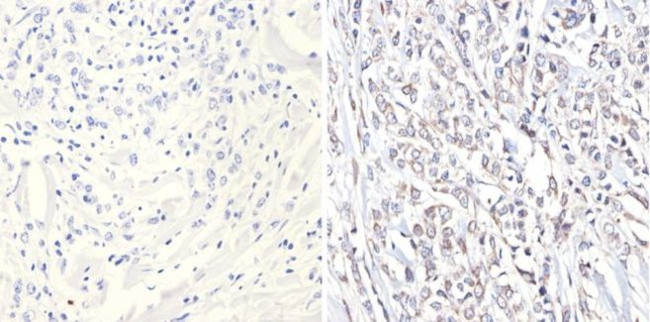

p38 MAPK gamma Antibody in Immunohistochemistry (Paraffin) (IHC (P))

p38 MAPK gamma Antibody (MA1-100) in IHC (P)

Immunohistochemistry analysis of MAPK12 showing positive staining in the nucleus and cytoplasm of paraffin-treated Human breast carcinoma (right) compared with a negative control in the absence of primary antibody (left). To expose target proteins, antigen retrieval method was performed using 10mM sodium citrate (pH 6.0), microwaved for 8-15 min. Following antigen retrieval, tissues were blocked in 3% H2O2-... View More {{ $ctrl.currentElement.advancedVerification.fullName }} 验证信息 View more